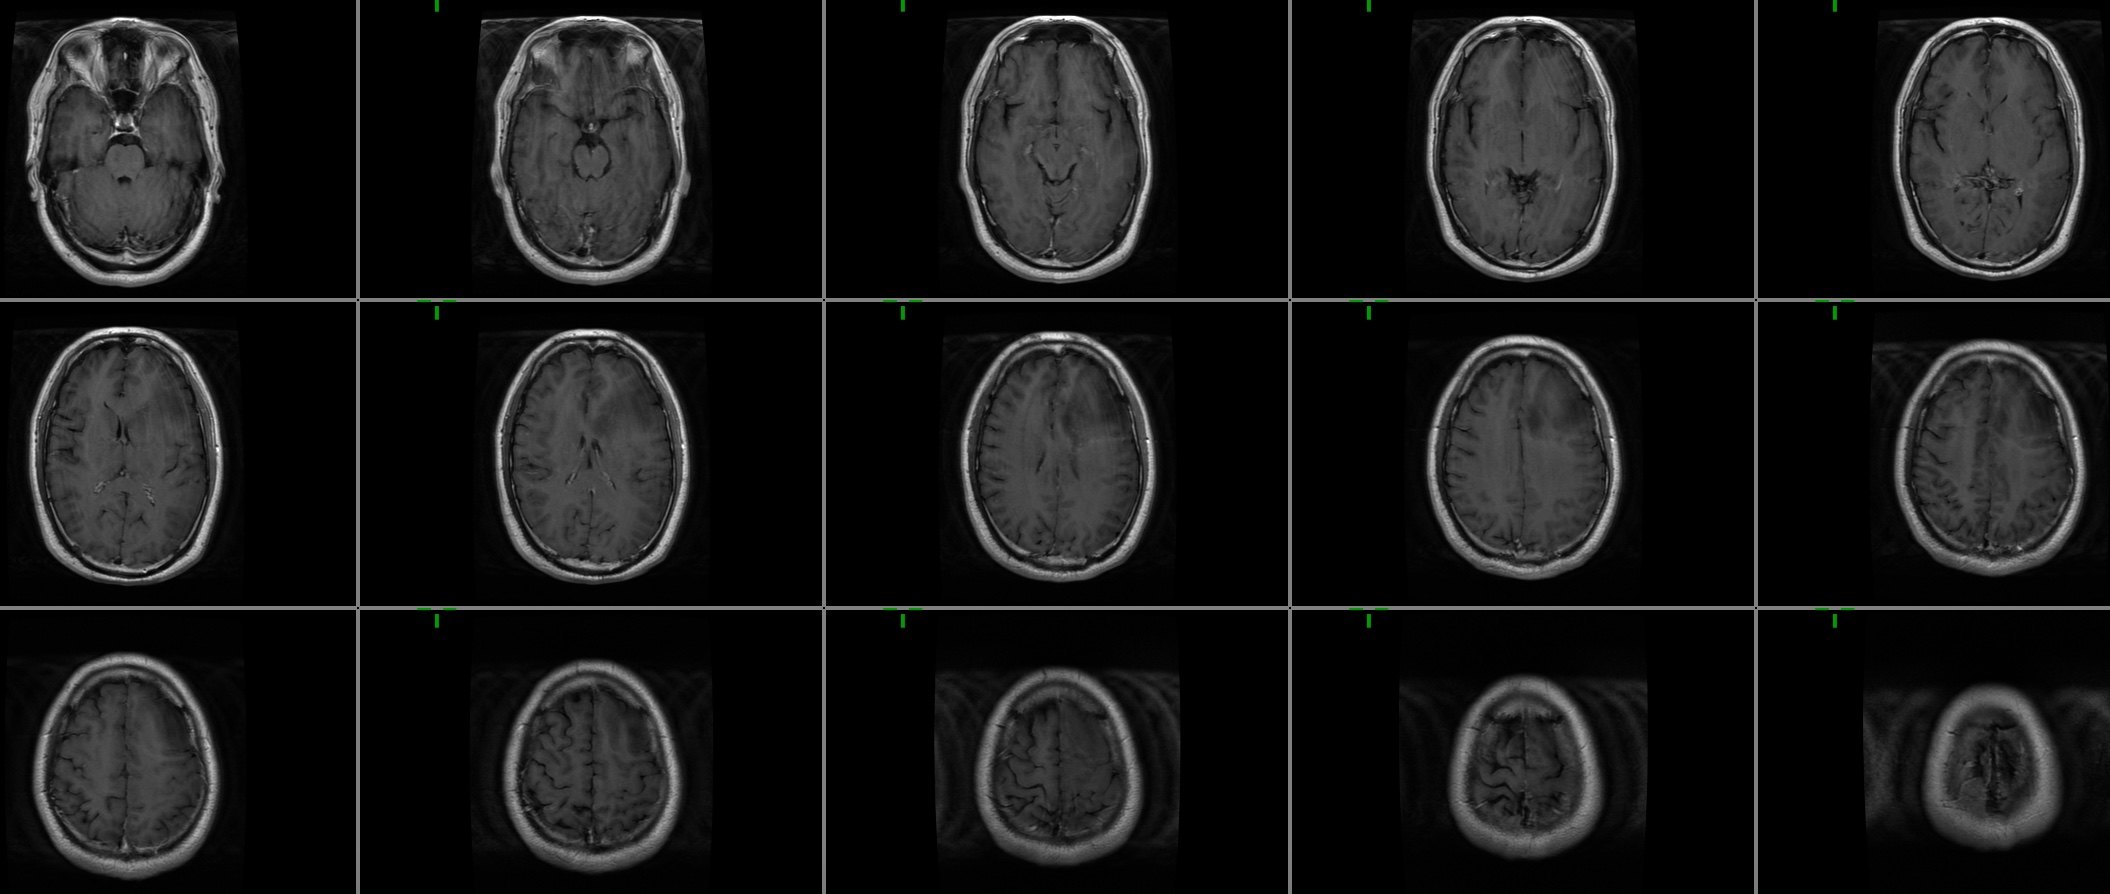

术前t1增强轴位.jpeg

图片尺寸2110x894